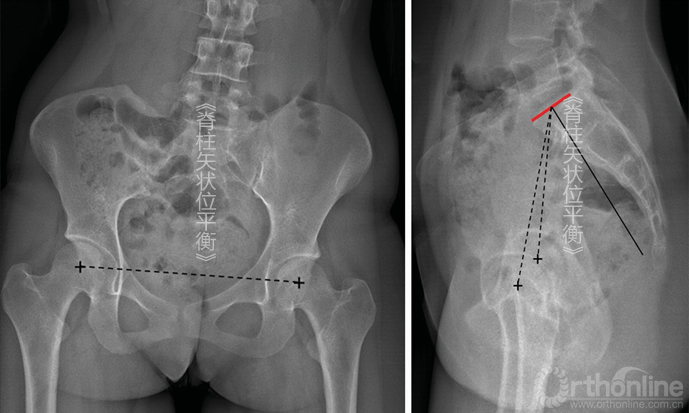

PI角由以下两条线构成:①骶骨上终板中点的垂线;②双侧股骨轴连线中点同骶骨上终板中点之间的连线(也可以为双侧股骨头连线中点同骶骨上终板中点之间的连线)(图5-1)。

图5-1 A.Duval-Beaupère所提出的骨盆几何参数,包括骨盆入射角(PI)、骨盆倾斜角(PT)、骶骨倾斜角(SS);B.通过KEOPS软件进行脊柱矢状位重建

医师在测量PI角时可能遇到很多困难。骶骨终板及前后边界通常容易分辨,但是因为传统的成像设备很难将双侧股骨头对齐,所以股骨头中点经常容易混淆:

①股骨头垂直移动(图5-2)。这是由于X线束的倾斜度与下肢长度的差异造成的。此时引用双侧股骨头连线中点线测量PI角是可以的。

图5-2 因为双下肢不等长导致股骨头股骨头垂直立线偏移,对PI的测量几乎没有影响

②股骨头水平移动(图5-3)。此时测量无法进行,其影响脊柱矢状位平衡分析。这是因为骨盆水平旋转,此时的X线不是真实的侧位片,且如果骨盆旋转较大,测量得到的PI角会受到影响,这样的影像便不能采纳。

图5-3 因骨盆旋转导致股骨头水平立线偏移,会导致PI测量结果误差较大